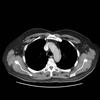

CT supine and prone

Date: 07/27/2013

Views: 3202